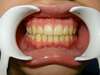

Intrabuccale face - Avant traitement 1 (25-01-2021) - 2

Intrabuccale face - Fin de traitement (24-09-2023) - 30